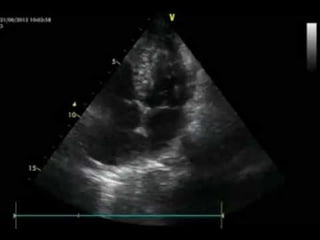

SUBCOSTAL